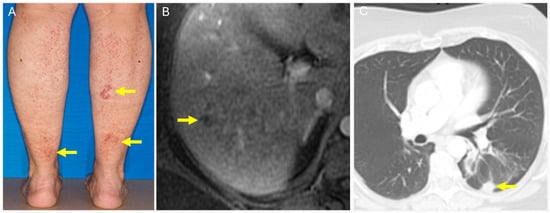

5.1. Type 1 Cryoglobulinemia

5.2. Necrobiotic Xanthogranuloma (NXG)